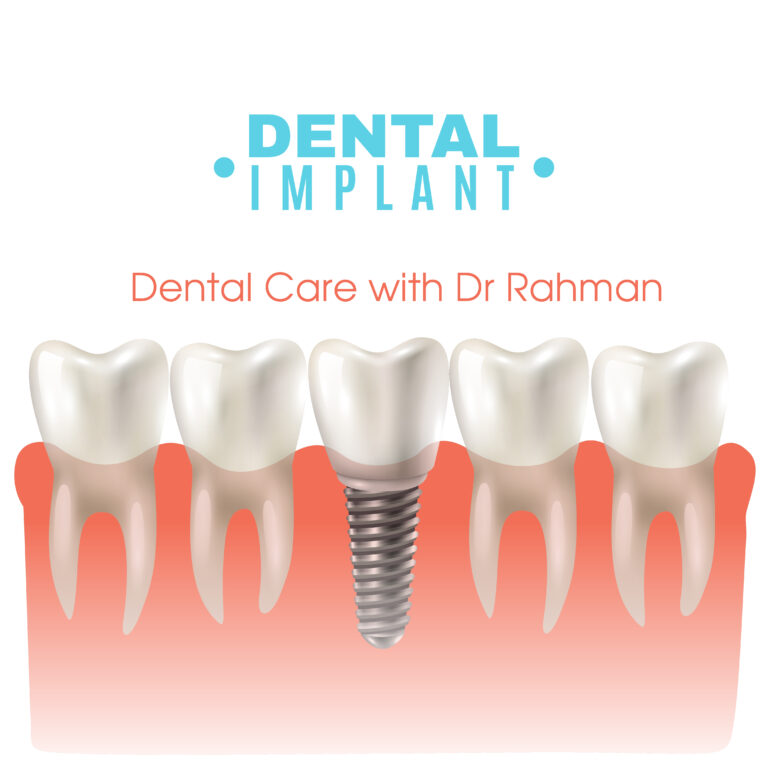

Dental implants are a durable and natural-looking solution for replacing missing teeth. Unlike dentures or bridges, implants involve a titanium post surgically placed into the jawbone, which acts as a secure foundation for a replacement tooth. Over time, the post fuses with the bone, creating a stable and long-lasting base for crowns, bridges, or dentures. Implants help preserve jawbone density, prevent shifting of nearby teeth, and restore the full function and appearance of natural teeth. Ideal for those seeking a permanent option, dental implants can significantly enhance both aesthetics and oral health. Dental Care with Dr Rahman is the best dental clinic in Banani Dhaka

Due to high success rate and aesthetic and functional similarity with natural teeth dental implant is most popular treatment of choice.

By proper assessment, planning and specialist clinician’s support we could provide you the desired service as the best dental implant clinic in Dhaka at Banani.

In Bangladesh, dental implants are widely regarded as a successful and practical option for replacing lost teeth. They offer a long-term solution with few drawbacks, ultimately enhancing your quality of life and self-esteem.